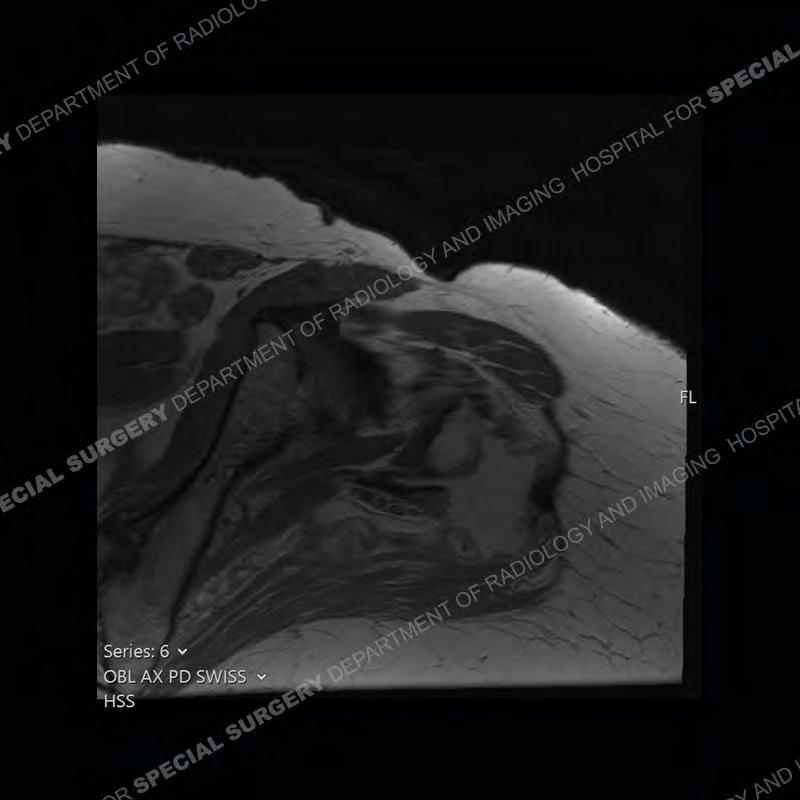

The radiograph is not particularly contributory in this case. The MRI demonstrates markedly abnormal architecture of the gluteus minimus and anterolateral band of the gluteus medius. Portions of the tendons are high signal, portions are highly attenuated, and portions are disrupted. A large, complex fluid collection is present in the adjacent soft tissue.

Diagnosis: Gluteal Tendinosis and Disruption with Complex Trochanteric Bursal Collection

Not as much of a diagnostic dilemma as many of the other cases shown but just a nice example of the pathology seen of the gluteal tendons and a cause of trochanteric pain. Although, frequently thought of in isolation, trochanteric bursitis or bursal thickening is much more commonly a reactive change to underlying pathology of the subjacent gluteal tendons. The gluteus medius is divided into a posterior band and an anterolateral band. Tendinosis and partial tearing very commonly will involve the gluteus minimus and especially the more posterior fibers and then propagate into the anterior lateral band of the gluteus medius. Involvement of the posterior band of the medius is much less common and engenders a marked degree of functional impairment.

The bursae about the greater trochanter can be a little bit confusing especially given the terminology. Trochanteric bursitis is implied to mean the subgluteus maximus bursa which is present deep to the maximus and just lateral/superficial to the trochanter. That is the bursa involved in this case. In this case the complexity of the bursa relates to the tendon tearing with inflammatory change and probably hemorrhage accounting for the complexity. Two other, less frequently involved bursa are also present. The subgluteus medius and subgluteus minimus bursa are found just deep to the named tendons. Although pathology does frequently follow the previously described pattern it is possible to have isolated pathology to either the medius or minimus.